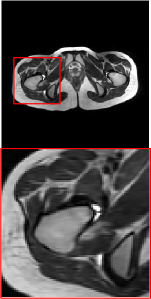

4.3 Qualitative results

Figure 5 provides the qualitative comparison of the various methods on the four datasets at a scale of 4. The top, second, third, and bottom rows are the SR results under the FastMRI, clinical brain, clinical tumor and clinical pelvic datasets, respectively. The red boxes indicate the zoom-in region of complicated anatomical structures along with their corresponding error maps. Note that the brighter textures in the error maps, the lower the quality of the reconstructed images. As can be seen, compared to methods based on Transformers and CNNs, diffusion-based methods like DisC-Diff and DiffMSR (Ours) are capable of reconstructing high-realistic images with promising reconstruction metric scores (PSNR and SSIM). Nevertheless, while DisC-Diff can reconstruct high-precision MR images, it does not preserve the structure present in the original HR images, introducing some additional information that can affect medical diagnosis. In contrast, our method combines DM and PLWformer, which can preserve the original image’s structure while restoring high-frequency information.

9 More Visual Comparisons

In this section, we present more visual qualitative comparisons. Figures 8, 9, 10, and 11 show the reconstruction results of each method in FastMRI, clinical brain, clinical tumor, and clinical pelvic, respectively. As can be seen, although DisC-Diff can reconstruct MR images with high-frequency information, it fails to preserve the structure and content of the original Target HR image effectively, resulting in image distortion. In contrast, our proposed DiffMSR can restore high-frequency information while preserving the structure of the original HR image, indicating the effectiveness of the joint use of DM and PLWformer.